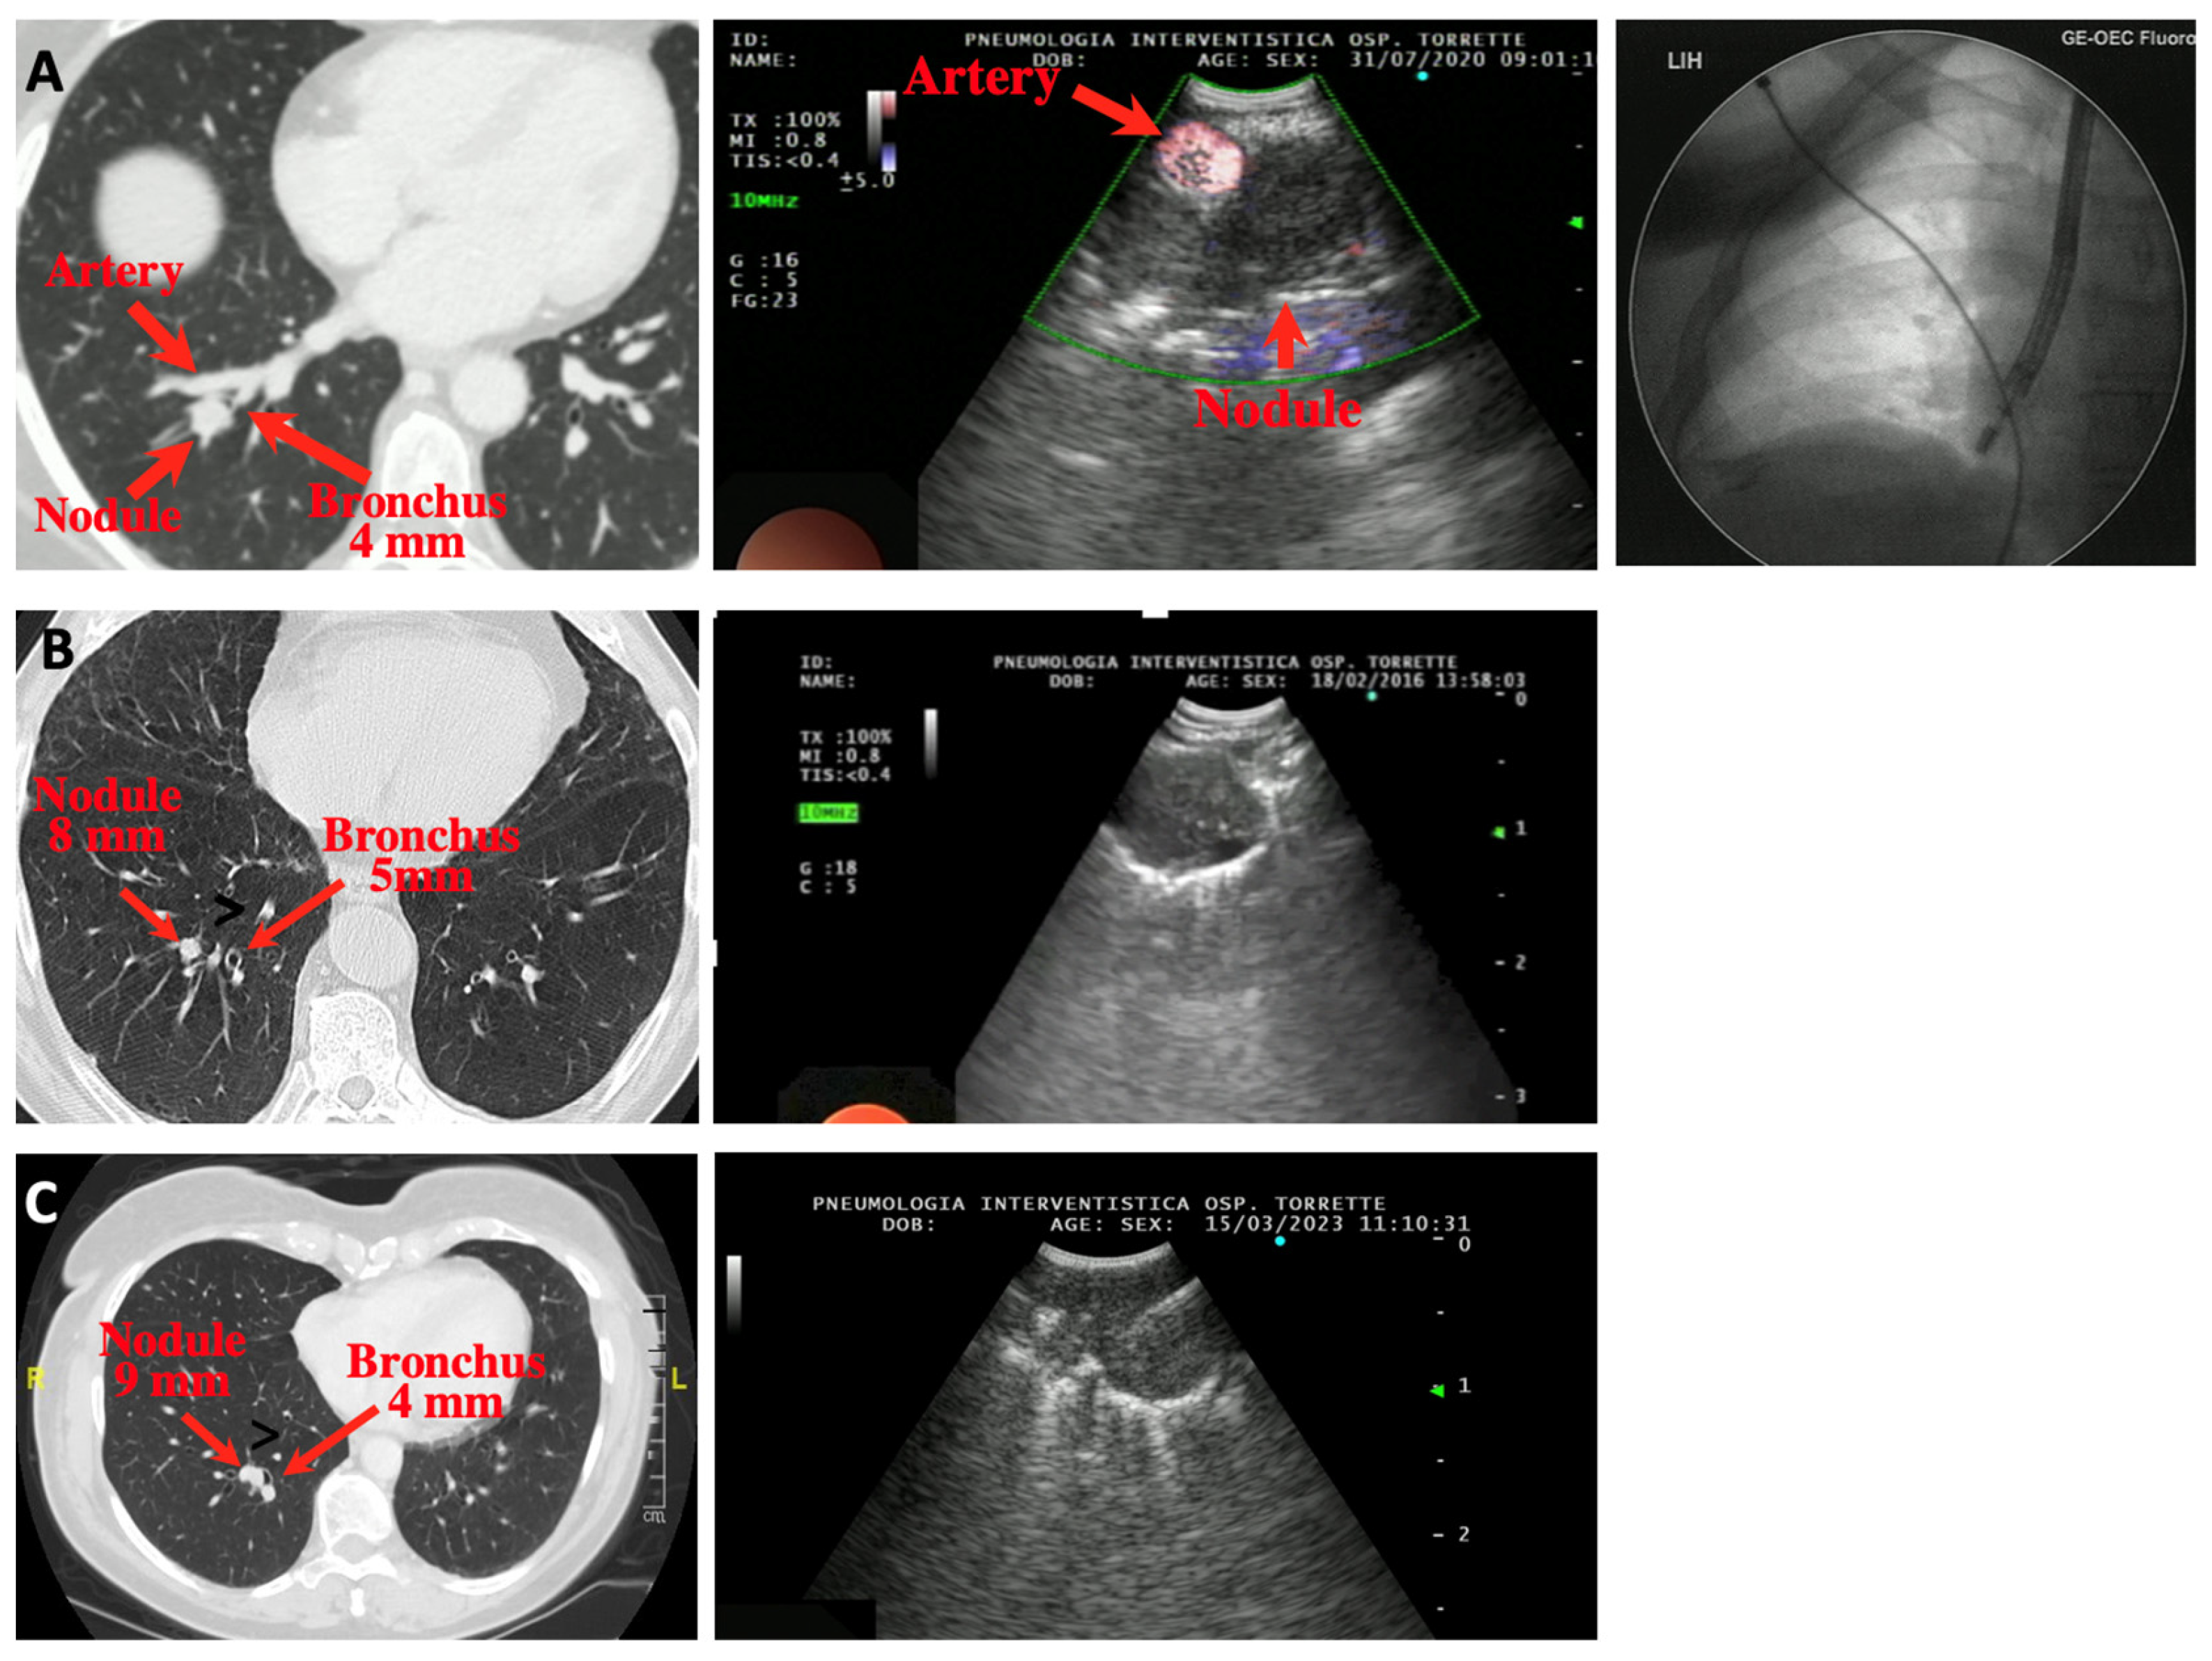

2. Materials and Methods

- pulmonary nodule located in the lower lobes, in an area adjacent to the subsegmental or a more distal bronchus;

- evidence at CT scan of an airway ≥ 3 mm in diameter adjacent or close (≤1 cm) to the nodule;

2.2. Procedure